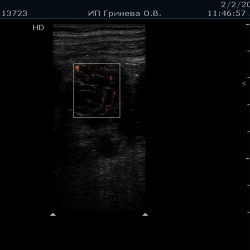

Пациент 65 лет с поликистозом обеих почек, креатинин 400.При Узи в области нижнего полюса между анэхогенными кистами лоцируется гипоэхогенное неоднородное образование с пери и интранодулярным...